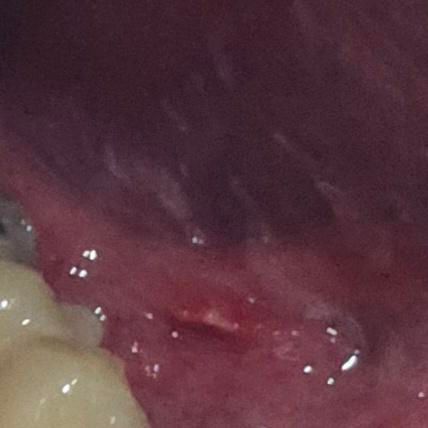

사진 첨부합니다. 혀 밑에 염증이 생겼는데 염증이 생기는 원인과 지금 생긴 염증의 이름이 있다면 알려주세요. 자연치료에는 얼마나 걸릴지도 여쭤봅니다

사진으로는 정확한 진단 불가능하며 병원 방문하셔서 직접 육안으로 진료 보셔야 합니다특히 올려주신 사진은 너무 어두워서 병변이 잘 안보여요. 확인 불가입니다

우선 말로 말씀하신 부분 관련 답변 드리자면 혀 밑에 생긴 염증은 보통 설하염(혀 밑 염증) 또는 구강 점막염의 일종일 가능성이 있습니다. 원인은 다양할 수 있는데, 대표적으로는 구강 위생 불량, 바이러스(특히 헤르페스), 세균 감염, 기계적 자극(예: 이물질, 잘못된 칫솔질), 영양결핍(특히 비타민 B군 부족), 스트레스 등이 있습니다.

때로는 치아나 틀니 문제, 혹은 알레르기 반응으로도 염증이 생길 수 있구요. 만약 염증 부위가 붓거나, 고름이 차거나, 통증이 심하면 세균성 감염이 진행된 것일 수도 있어요

자연치료는 염증의 원인과 심한 정도에 따라 다르지만, 가벼운 경우라면 보통 1주일 내외로 저절로 호전됩니다. 이 기간 동안은 구강을 청결히 하고, 자극적인 음식(매운 것, 뜨거운 것, 딱딱한 것)을 피하는 것이 중요합니다. 염증이 2주 이상 지속되거나 통증이 심해지면 반드시 병원을 방문하여 진료를 받아야 합니다